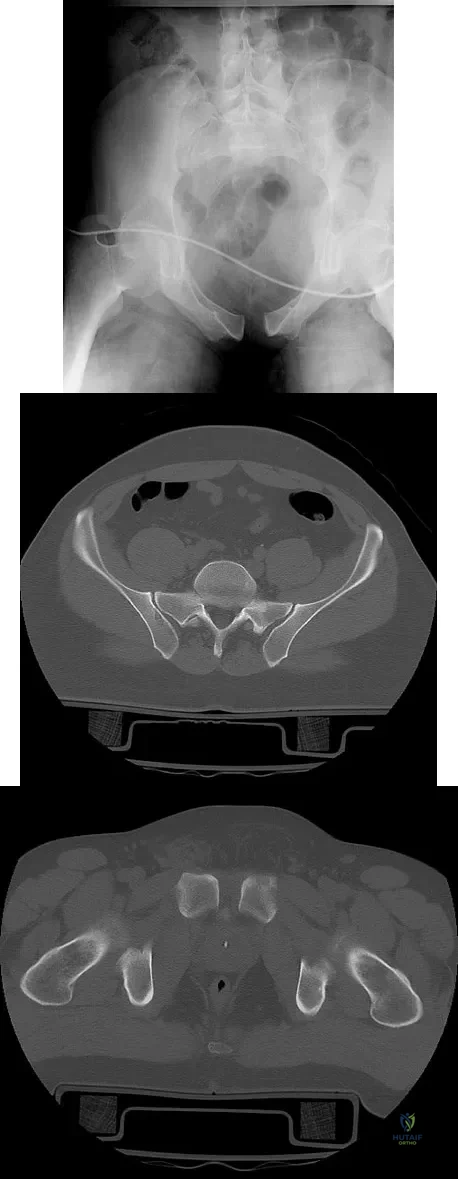

A 28-year-old cowgirl was injured while herding cattle 1 week ago. A radiograph and CT scans are shown in Figures 13a through 13c. What is the most appropriate management for this injury?

Explanation